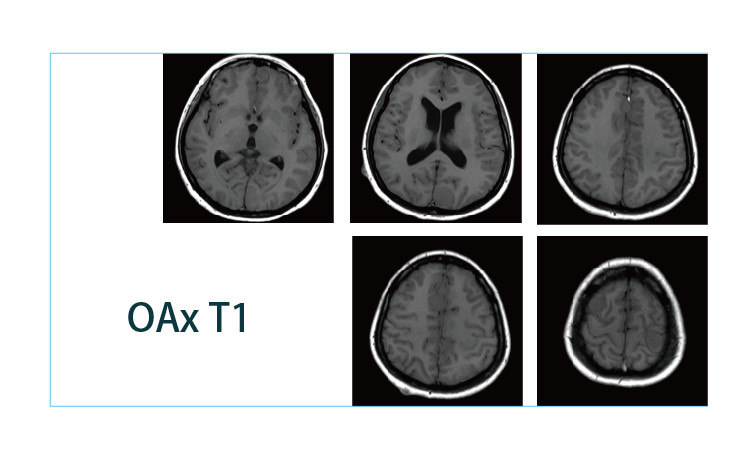

【朗润影像档案】磁共振影像病例分享(编号20190426)

【朗润影像档案】磁共振影像病例分享(编号20190419)

【朗润影像档案】磁共振影像病例分享(编号20190412)

【朗润影像档案】磁共振影像病例分享(编号20190405)